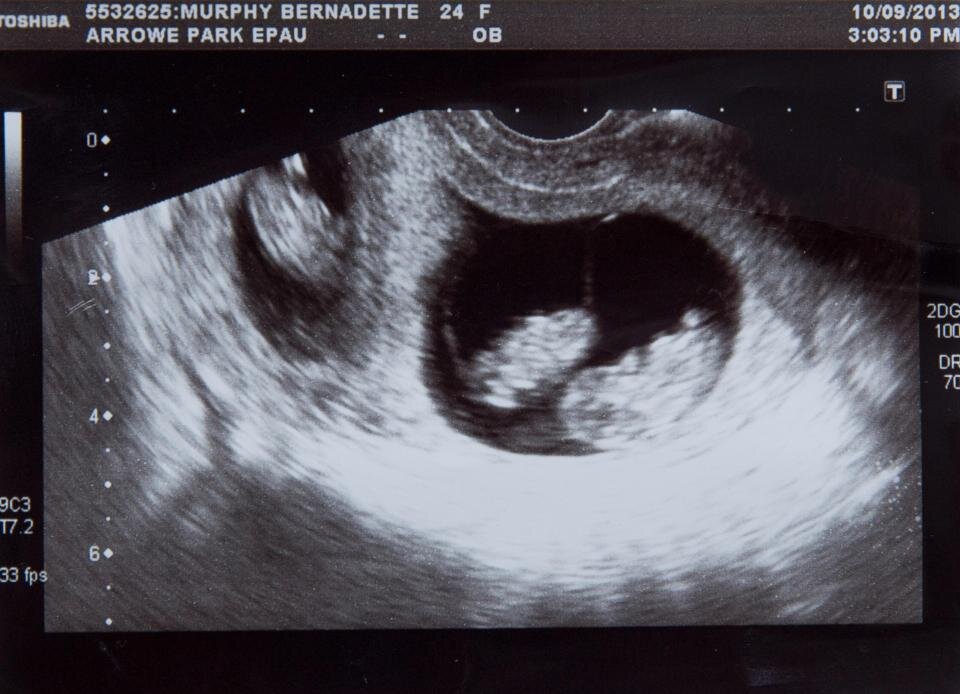

На 16 неделе ей сказали, что двое малышей из тройни погибли. Врачи предложили делать аборт. Но героиня нашей истории решила, что спасет сына. Несмотря ни на что. Все начиналось радужно. 29-летняя Бернадетт Мерфи узнала, что у нее будут тройняшки - мальчики. Они с мужем очень хотели детей и радовались тройне. Родители уже успели дать им имена - Джеймс, Джозеф и Найл. Последние были однояйцевыми близнецами - похожими друг на друга как две капли воды. На 12 неделе беременности врач был обеспокоен ростом Найла по сравнению с его близнецом Джозефом. После этого за малышами начали пристально следить. Обследования назначили раз в неделю. Спустя 3 недели появилось подозрение на фето-фетальный трансфузионный синдром. "Когда я пошла на 16-недельное УЗИ, я объяснила, что со времени моего предыдущего сканирования у меня начались судороги вниз по левой стороне и несколько ударов ногами. Я знала, что что-то было не так. Я помню, как консультант схватил меня за руку, и мне сказали, что близнецы погиб

На 12 неделе беременности врач был обеспокоен ростом Найла по сравнению с его близнецом Джозефом. После этого за малышами начали пристально следить. Обследования назначили раз в неделю. Спустя 3 недели появилось подозрение на фето-фетальный трансфузионный синдром.

"Когда я пошла на 16-недельное УЗИ, я объяснила, что со времени моего предыдущего сканирования у меня начались судороги вниз по левой стороне и несколько ударов ногами. Я знала, что что-то было не так. Я помню, как консультант схватил меня за руку, и мне сказали, что близнецы погибли".

Мальчики погибли из-за фето-фетального трансфузионного синдрома. Это состояние возникает во время беременности, когда между близнецами с общей плацентой идет неравномерное распределение крови. Кровь к одному практически не поступала, что привело к задержке развития, проблемам с почками и легкими. А ко второму поступала, но в огромном количестве, что стало причиной сердечной недостаточности.